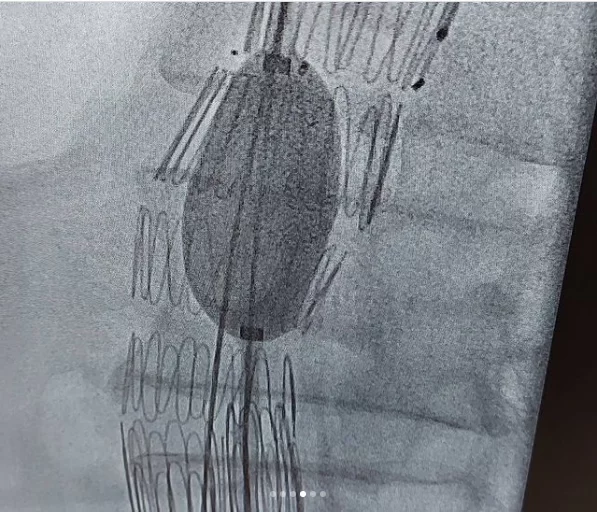

این بیماران با احساس ضربانات مداوم در شکم و درد و گاهاً بدون علامت در معرض خطر پارگی رگ اصلی بدن به نام آئورت ومرگ ناگهانی هستند .دیروز در کمتر از یکساعت بدون جراحی ، استنت هایی که پوشش دیواره ای دارند را مثل لوله داخل ناحیه آنوریسم/یا گشاد شده، تعبیه کردیم و آئورت به سایز نرمال برگشت.